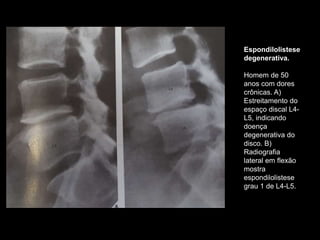

Espondilolistese

degenerativa.

Homem de 50

anos com dores

crônicas. A)

Estreitamento do

espaço discal L4-

L5, indicando

doença

degenerativa do

disco. B)

Radiografia

lateral em flexão

mostra

grau 1 de L4-L5.